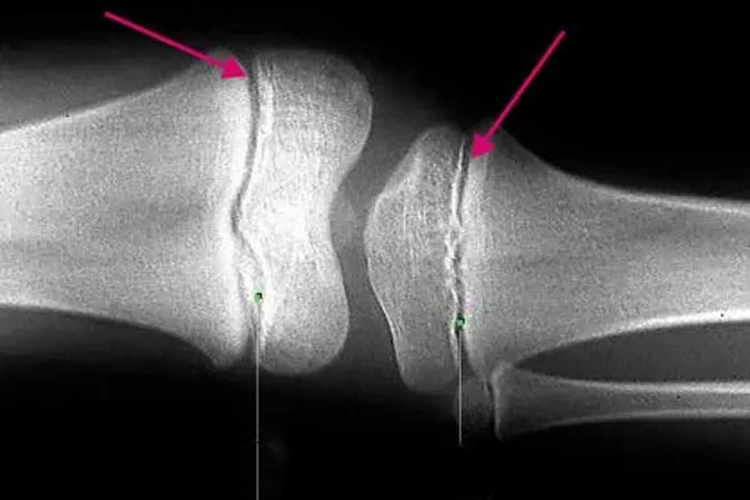

腿部骨骺线没有闭合时,腿部长骨的X线检查可见一条透明光带,常说明机体正处于生长发育进程中,此时需注意营养补充。

腿部骨骺线没有闭合时通过X线检查可发现股骨、胫骨、腓骨的长骨两端有一条较宽的透光带,在18-22岁时该透明光带会逐渐变窄,直至闭合消失,有时可能会残留一条致密线痕迹。